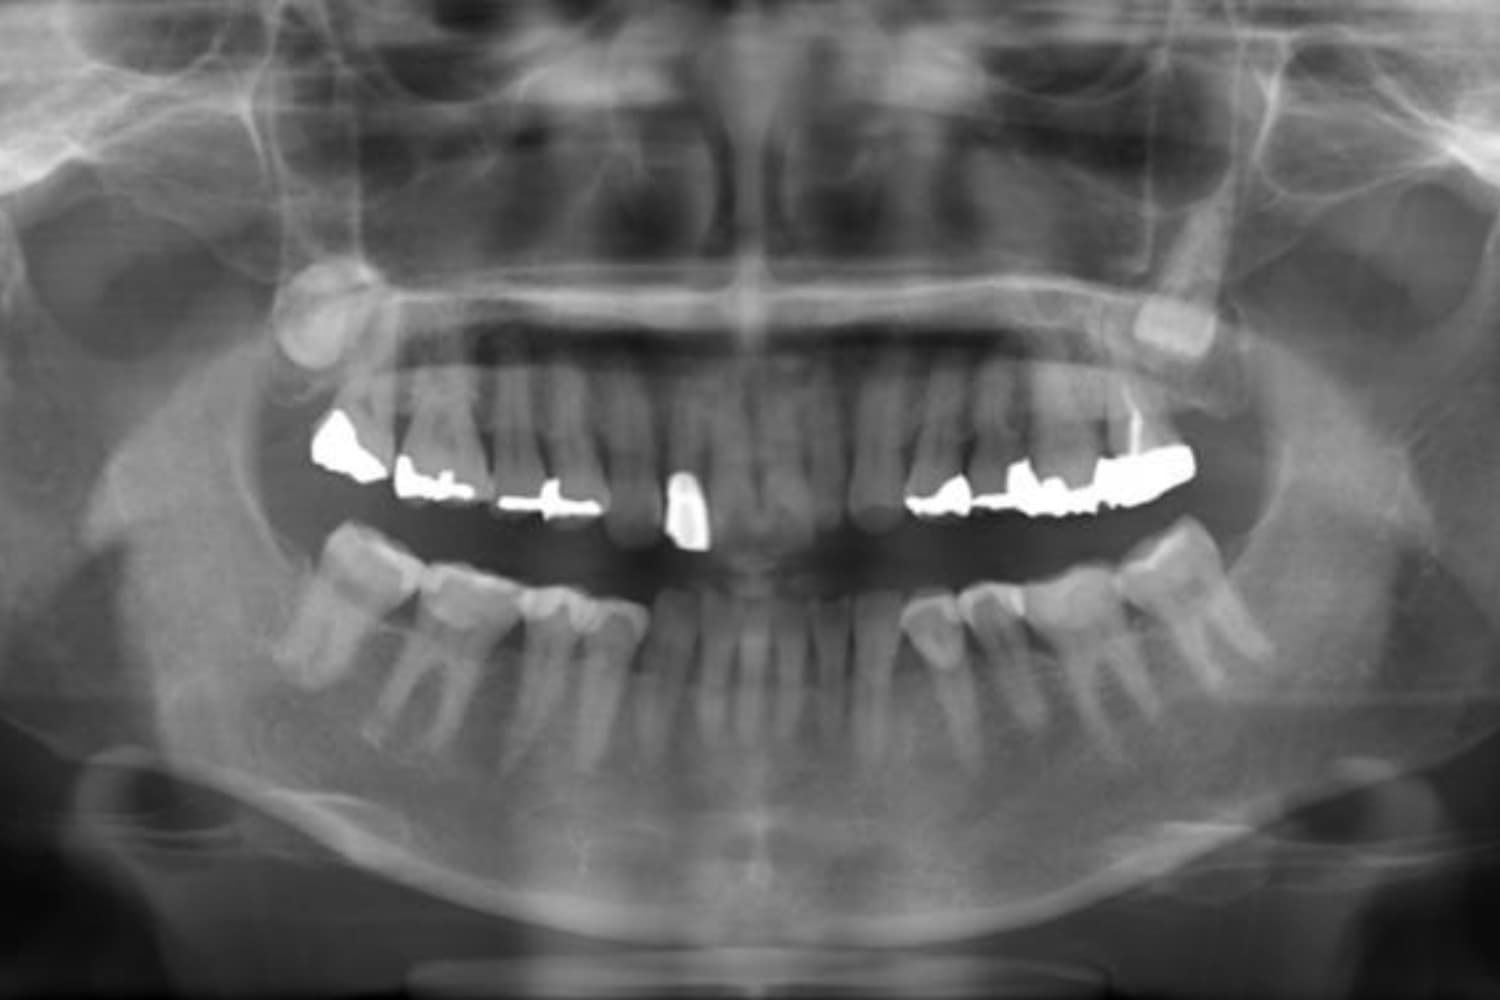

上顎前歯1本欠損症例(2)

Before

歯の根の先に炎症が広がっていたため抜歯をおこないました。その後、土台となる骨を作る処置をおこなった後、インプラントを1本埋入しました。

年齢

70歳

性別

女性

主訴

歯肉の腫れ

治療期間

10ヵ月

費用

60万円